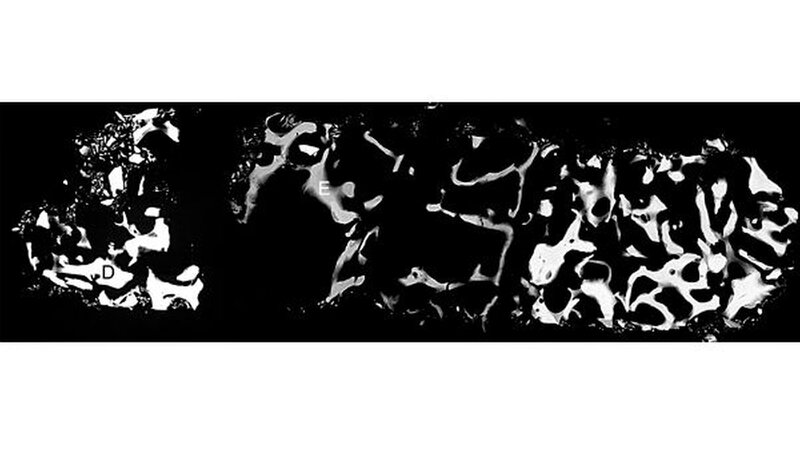

Ayna dokumentierte die chirurgisch aufwendige Behandlung eines Duisburger Patienten. Dabei handelte es sich um den Knochenaufbau in der Kieferhöhle, den Sinuslift. 14 Jahre nach dem Einsatz des anorganischen Rinderknochen-Materials (ABBM) führte Ayna eine histologische und eine mikroradiografische Untersuchung des eingelagerten Materials durch.

Ergebnis: Das Material wurde auch nach diesem langen Zeitraum nicht vom Körper aufgelöst. Vielmehr kam es zu einer erfolgreichen Knochenneubildung. Aynas Untersuchung weist in dem aufgebauten Knochenbereich einen Eigenknochenanteil von mindestens 14 Prozent nach. Die histologischen Untersuchungen lassen darauf schließen, dass der Sinuslift in den zentralen Bereichen aus vitalem Knochen besteht.